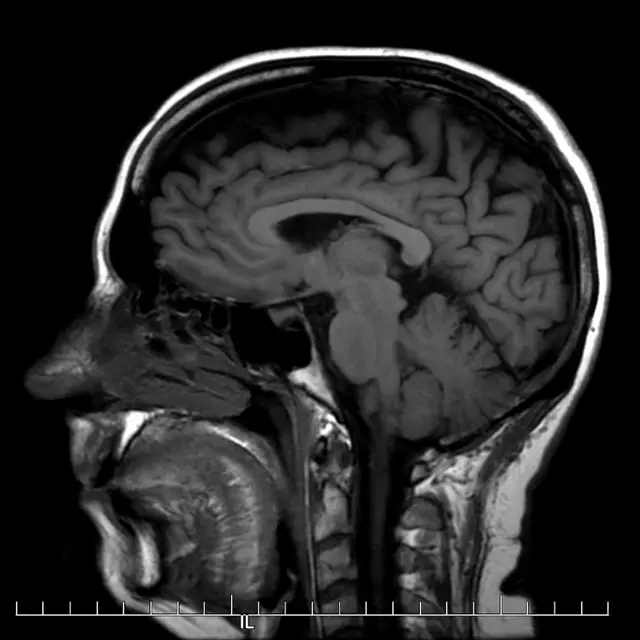

Un escáner cerebral mostró una lesión en el lado derecho de mi cerebro. No estaba claro exactamente qué significaba eso. El neurólogo me dijo que si bien podría ser una señal temprana de esclerosis múltiple, también podría ser nada de qué preocuparse.

Cuando me volví insensible a gran parte de mi cuerpo durante varias semanas, me hicieron otro escáner cerebral y finalmente me diagnosticaron EM.

Esta vez fue una nueva lesión en el tronco cerebral la causa de la recaída.

El tronco encefálico es una de las partes más importantes del cerebro: regula el sistema nervioso central y controla funciones esenciales como la respiración, la deglución, la frecuencia cardíaca, la presión arterial y la conciencia.

Una de las pruebas clave para los pacientes que participan en los ensayos o que reciben dicho tratamiento en el sistema de salud público es un escáner cerebral que debe mostrar lesiones activas e inflamatorias en el cerebro.

Mi escáner no mostró mostró lesiones activas e inflamatorias en el cerebro, sugiriendo al equipo que no sería una buena candidata para un trasplante de células madre.

Sin embargo, mi último escáner cerebral muestra que, hasta el momento, no tengo nuevas lesiones en el cerebro.